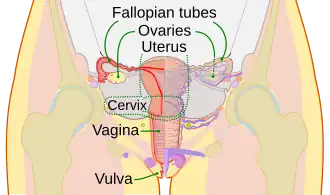

The purpose of the reproductive system is to reproduce and nurture the growth of offspring. The functions include the production of germ cells and hormones.[39] The sex organs of the male reproductive system and the female reproductive system develops and mature at puberty. These systems include the internal and external genitalia.

The female inner sex organs are the two ovaries, their fallopian tubes, the uterus, and the cervix. At birth there are about 70,000 immature egg cells that degenerate until at puberty there are around 40,000. No more egg cells are produced. Hormones stimulate the beginning of menstruation, and the ongoing menstrual cycles.[40][42] The female external sex organs are the vulva (labia, clitoris, and vestibule).[43][40]